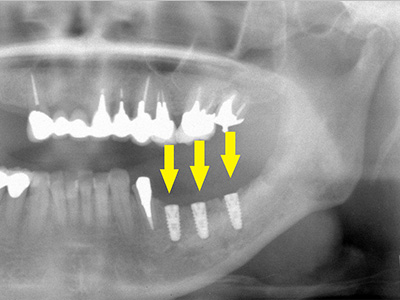

骨移植後数か月待って、移植した骨片が周囲骨と一体化した後、インプラントを埋入します。

骨の高さが十分に確保され神経を傷つけることなく、安全にインプラント埋入手術ができます。

写真が、インプラント埋入手術後、右写真が上部構造装着後のレントゲン写真です。 -